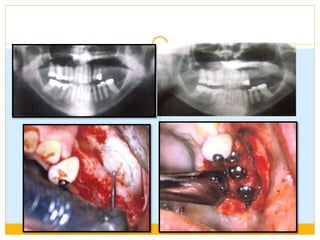

Inform patient about bone loss

DIVISION C(COMPROMISED BONE) Deficient in one or more dimensions  Resorption first occurs in width .The bone is called C-w  Then in height. The bone is called C-h  Posterior maxilla VS Anterior maxilla  Posterior mandible VS anterior mandible.

 Dimensions unfavorable in Width (c-w) :0 to 2.5mm  Height(c-h)-<12mm  Angulation (c-a)>30 degrees  CHS > 15mm